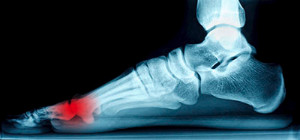

Heel Pain 101

The heel is designed to absorb the impact of body weight, and when pain develops, it can be disabling and affect other aspects of the body and life. Heel pain is usually the result of small repetitive injuries that are unable to heal, which then form into a bigger mechanical issue. These issues can include plantar fasciitis, heel bumps, tarsal tunnel syndrome, a fracture, Achilles tendonitis or heel spurs. Some self-care options for heel pain include wearing comfortable shoes, wearing shoes with good cushioning, minimizing walking on hard surfaces, or losing weight. If heel pain lasts longer than a few weeks, it is important to consult with a podiatrist in case the injury is more severe. A podiatrist will be able to properly diagnose and treat the source of the heel pain.

Causes of Heel Pain

Heel pain is often associated with plantar fasciitis. The plantar fascia is a band of tissues that extends along the bottom of the foot. A rip or tear in this ligament can cause inflammation of the tissue.

Achilles tendonitis is another cause of heel pain. Inflammation of the Achilles tendon will cause pain from fractures and muscle tearing. Lack of flexibility is also another symptom.

Heel spurs are another cause of pain. When the tissues of the plantar fascia undergo a great deal of stress, it can lead to ligament separation from the heel bone, causing heel spurs.